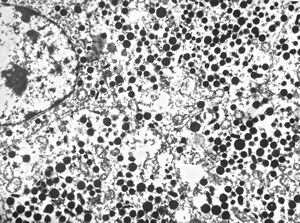

F, 71y. | carcinoid … metastasis to lymphonode